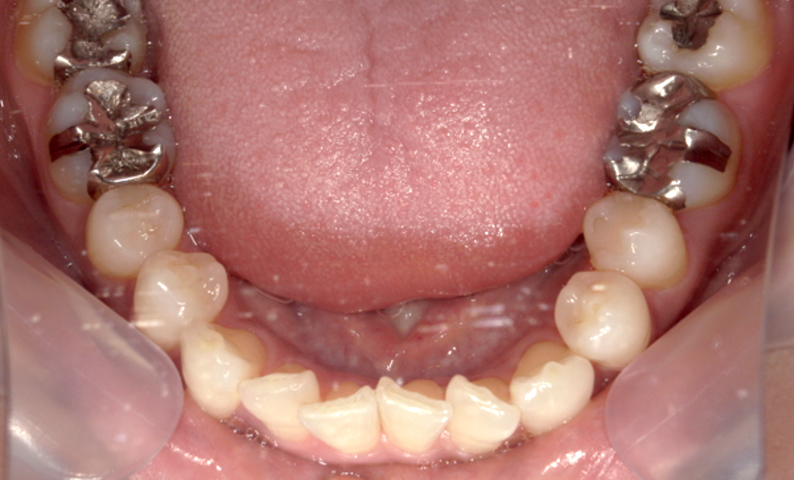

症例_001 前歯「捻転歯」症例

治療期間:6ヶ月金額:48万円+税20代女性少しのねじれ捻転歯下の八重歯

| Before | After |

|---|---|

|